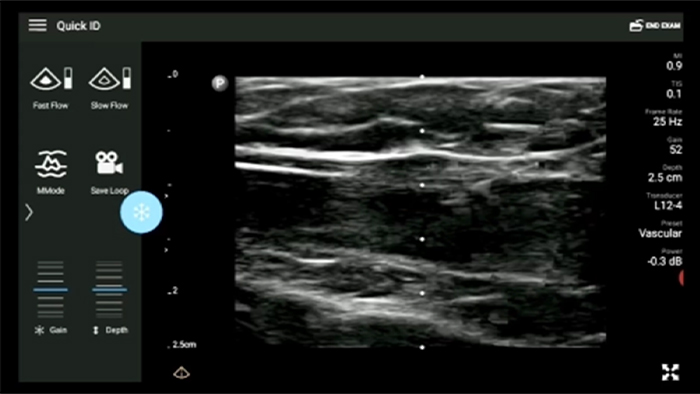

Lleve el ultrasonido a la cabecera del paciente

El uso de Lumify junto a la cama de sus pacientes puede ser una herramienta valiosa para determinar el estado del contenido estomacal y puede reducir el riesgo de aspiración pulmonar. En conjunto, esto puede reducir el riesgo de complicaciones por anestesia.

Transductor de matriz lineal de banda ancha Lumify L12-4